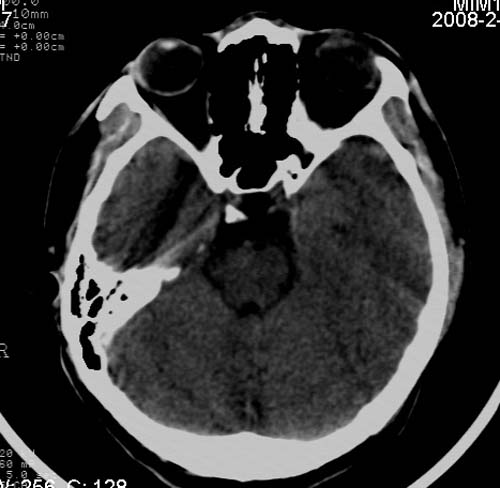

男,17岁,3天前与人斗殴,自述头痛、头晕。无恶心、呕吐,无阳性体征,一般情况良好。

病灶以钙化为主,无明显占位效应,病灶周围无水肿,这种情况应该是脑血管畸形,最多见的是动静脉畸形,其次是海绵状血管瘤.

病人较年轻,有头疼、头晕症状,动静脉畸形可能性大。